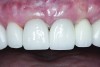

Fig 19 and Fig 20. Four-month follow-up appointment. The soft tissues had healed within normal limits (Fig 19), and the patient was pleased with the esthetic outcome of the definitive restoration (Fig 20).

The crown was inserted and secured with a luting composite (Multilink® Automix, Ivoclar Vivadent) (Figure 17); a radiograph confirmed complete removal of excess cement (Figure 18). At the 4-month follow-up appointment, the soft tissues were healed within normal limits, and the patient was pleased with the esthetic outcome of the definitive restoration (Figure 19 and Figure 20).